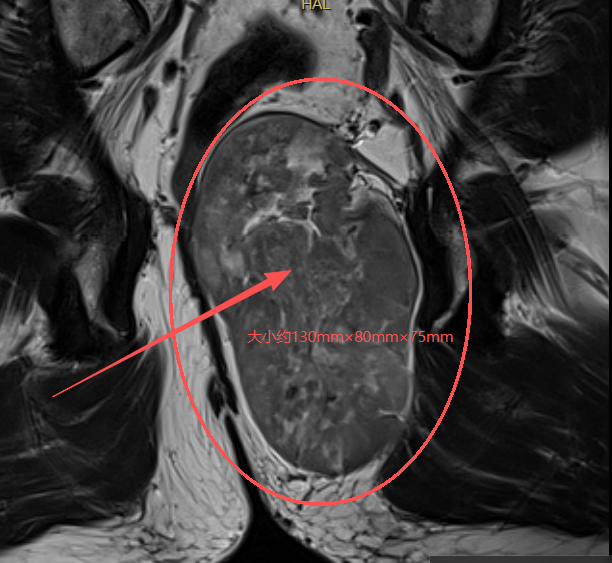

在南京市中医院,核磁检查显示:李先生直肠后方尾骨前方见不均质肿块影,大小约130mm×80mm×75mm(上下径×前后径×左右径),直肠及前列腺均受压移位。

南京市中医院肛肠科团队主任中医师樊志敏教授解释,该肿瘤体积巨大,肿瘤压迫直肠导致患者出现大便难解等不适症状,且肿瘤所处位置极为特殊,深居于骶骨与直肠之间的极狭窄间隙,边界不清,与骶骨、直肠、前列腺紧密相连,周围密布支配排便、性功能的神经丛及关键血管,稍有不慎,便可能引发大出血、神经损伤、直肠损伤、肠瘘、前列腺损伤出血等严重后遗症,手术难度和风险堪称临床难题。“正因如此,李先生几经周折,最终就诊于我院。”樊志敏教授说。